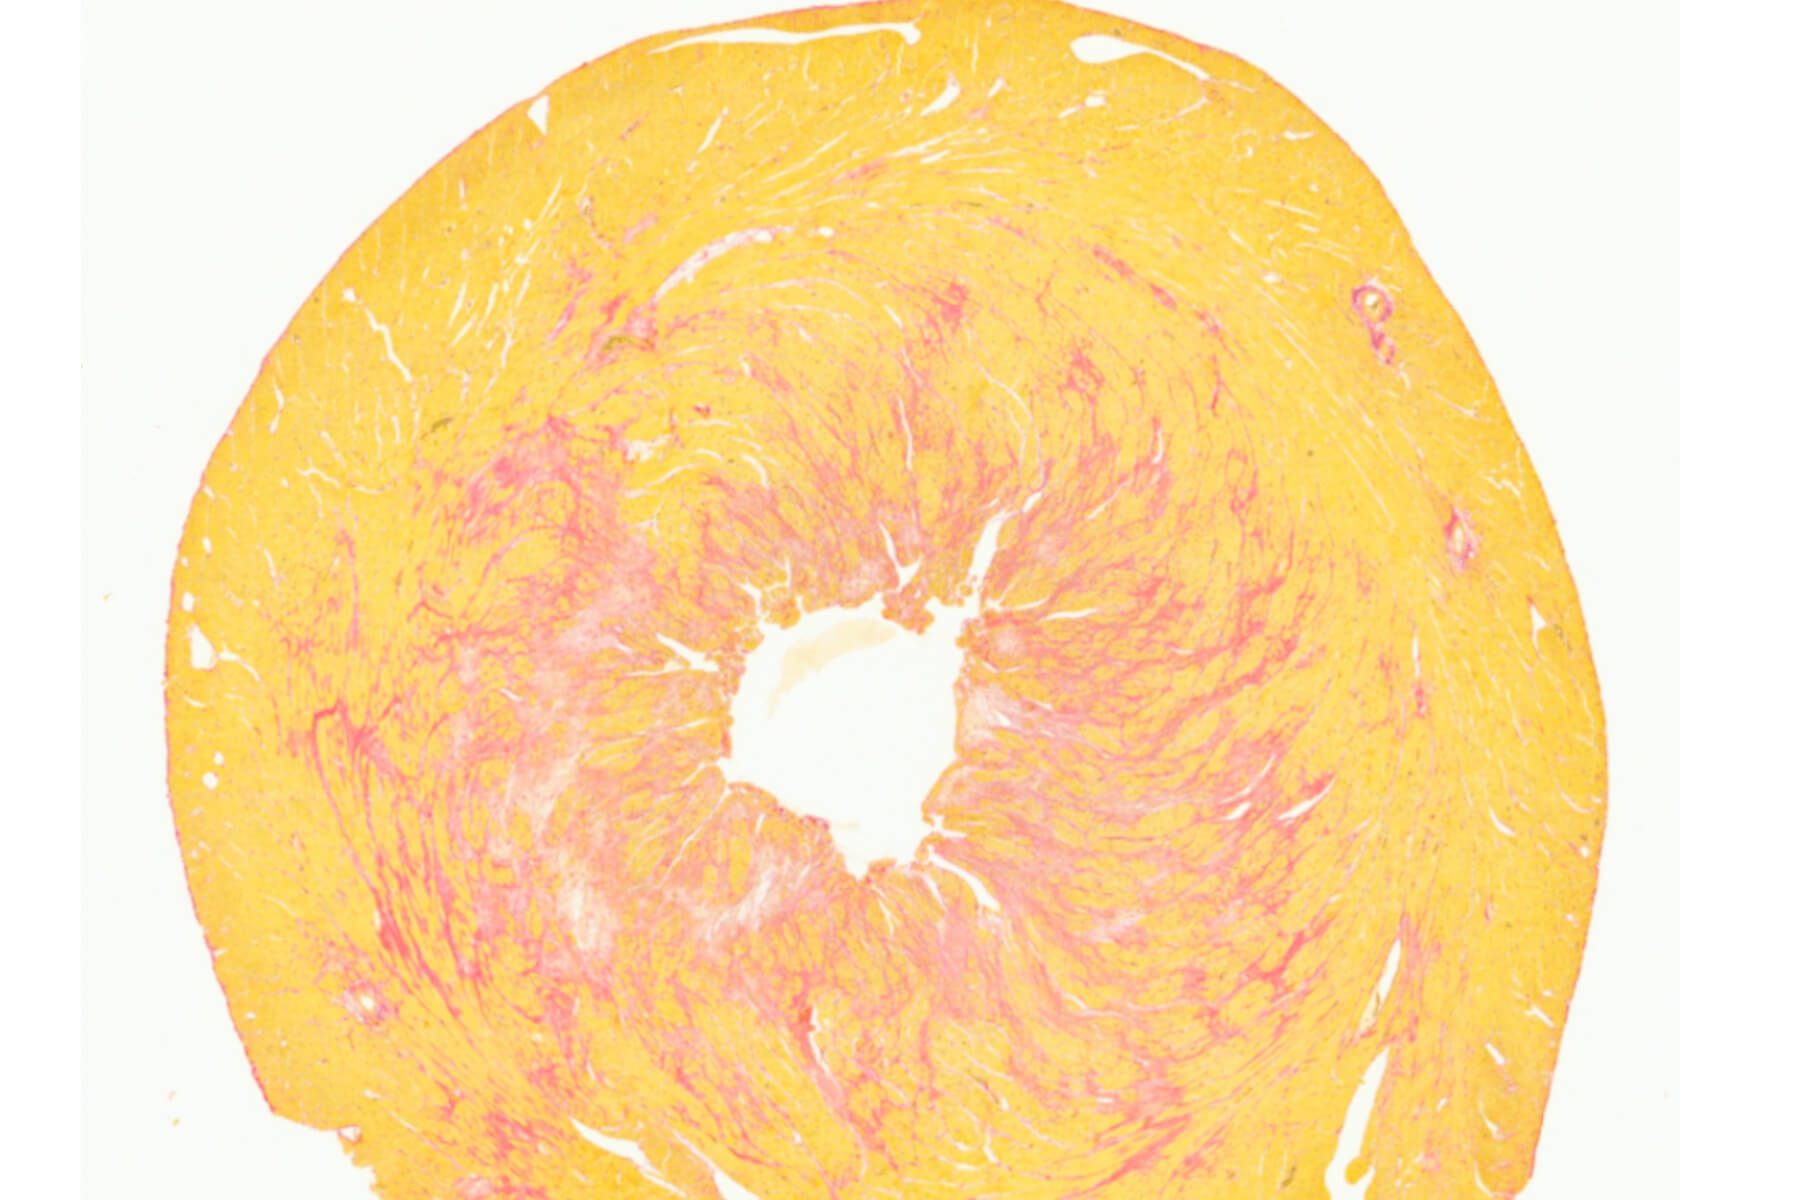

Immunohistochemistry, Immunofluorescence, and Histology

SYNCROSOME conducts preclinical pharmacology studies combining CRO‑level industrial standards with the scientific expertise of a research laboratory. We offer a full range of in vivo services, from standard to customized studies: lead optimization, POC, PK/PD, biomarker discovery, to meet your specific needs. We have three main areas of expertise to support your developments: right‑heart diseases (pulmonary hypertension), left‑heart diseases (myocardial infarction, HFpEF), and thrombotic diseases.